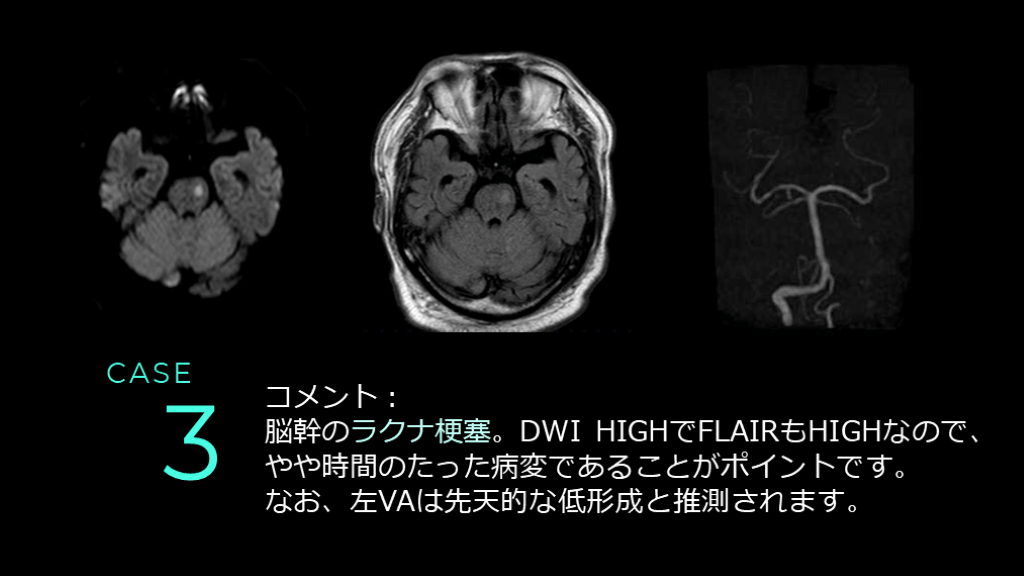

CASE 3 DWI FLAIR T2*

CASE 3 DWIでは左側の脳幹に高信号病変を認める。 同病変は、FLAIRではやや高信号を呈している。

CASE 3 MRAでは前方循環系はICAの口径不整が認められる。 後方循環系は、左のVAが右より細く描出されている。

CASE 3 コメント: 脳幹のラクナ梗塞。DWI HIGHでFLAIRもHIGHなので、やや時間のたった病変であることがポイントです。 なお、左VAは先天的な低形成と推測されます。